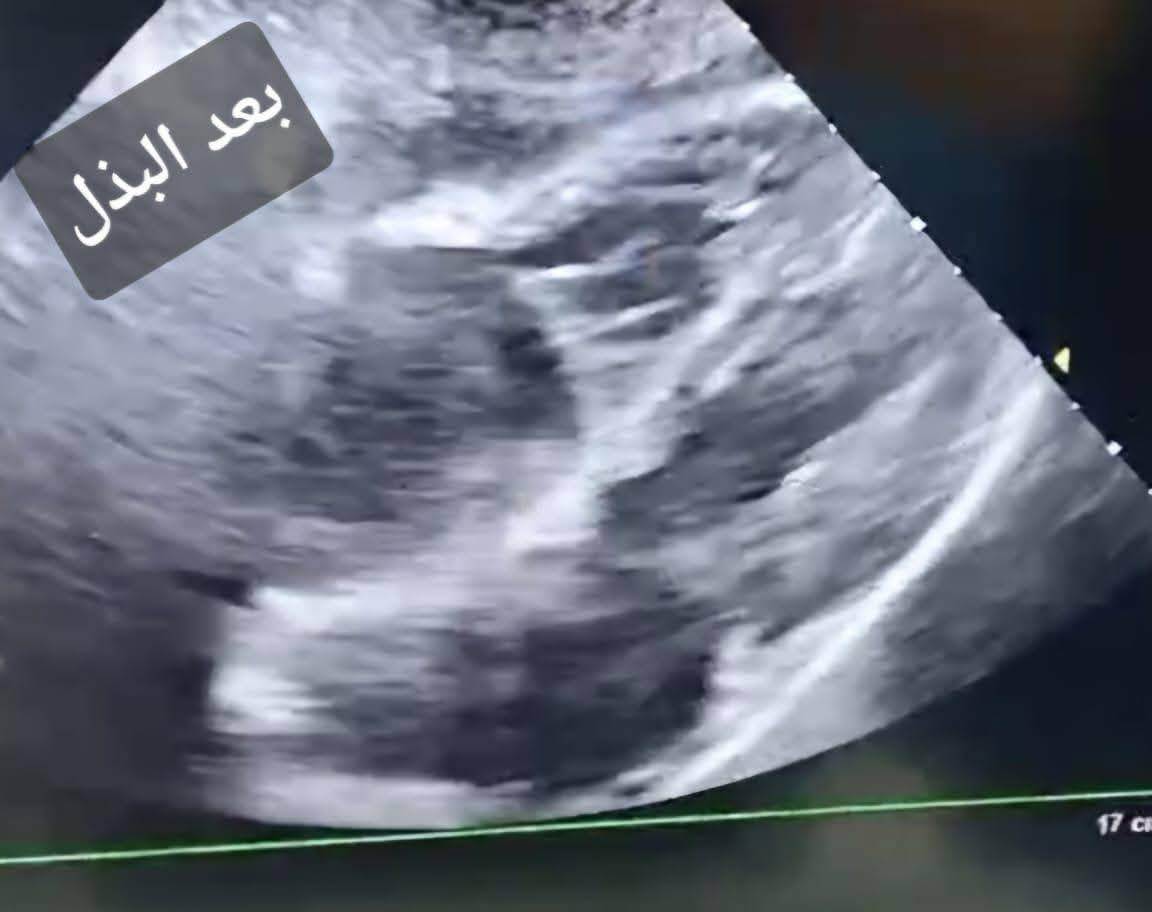

ومع المتابعة الدقيقة والمرور الطبي المنتظم، لاحظ الأطباء ارتفاعًا حادًا في معدل نبضات القلب، ما استدعى تحركًا فوريًا وإجراء رسم قلب كهربائي (ECG) وفحص الموجات الصوتية على القلب (Echocardiography)، لتكشف الفحوصات عن ارتشاح بالغشاء التاموري مصحوب بتأثير ضاغط على عضلة القلب، وهي حالة حرجة تتطلب تدخلًا عاجلًا دون أي تأخير.

وخلال ثوان معدودة، جرى التنسيق السريع مع قسم قسطرة القلب، حيث تولّى الفريق الطبي بقيادة الدكتور أحمد صبحي المدرس بالقسم، وبمشاركة الدكتور عبدالرحمن أحمد الخطيب الأخصائي، تجهيز الحالة ونقلها بشكل عاجل، ليتم تنفيذ بذل فوري للغشاء التاموري (Pericardiocentesis) داخل قسم القسطرة، في أول إجراء من نوعه يُنفذ بالقسم منذ إنشائه.

وأسفر التدخل الدقيق والسريع عن سحب ما يقرب من 700 مل من السوائل من الغشاء التاموري، وهو ما انعكس مباشرة على الحالة العامة للمريض، حيث ارتفعت نسبة تشبع الأكسجين واستقرت العلامات الحيوية بصورة ملحوظة، في مشهد جسّد بوضوح قيمة القرار الطبي السريع المبني على خبرة علمية وتكامل مهني.